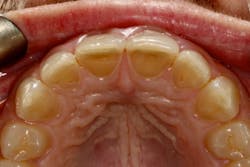

We digitally analyze our esthetics and smile design using the Dawson Diagnostic Wizard (the Dawson Academy). One of our biggest esthetic concerns in this case was caused by a functional issue. As you can see in the photos (figures 1 and 2), the patient has significantly more attritional wear on the right side versus the left. Due to the wear, the right anterior teeth have suffered from more compensatory eruption than the left, which results in uneven gingival architecture and esthetically displeasing length-to-width ratios of the anterior teeth (figures 3 and 4).

When we start to look at our occlusal shots (figures 5 and 6), it is obvious that we have some acidic erosion into dentin as well as significant wear facets from attrition. The pulp chambers of teeth Nos. 8 and 9 are now visible due to the loss of lingual tooth structure.